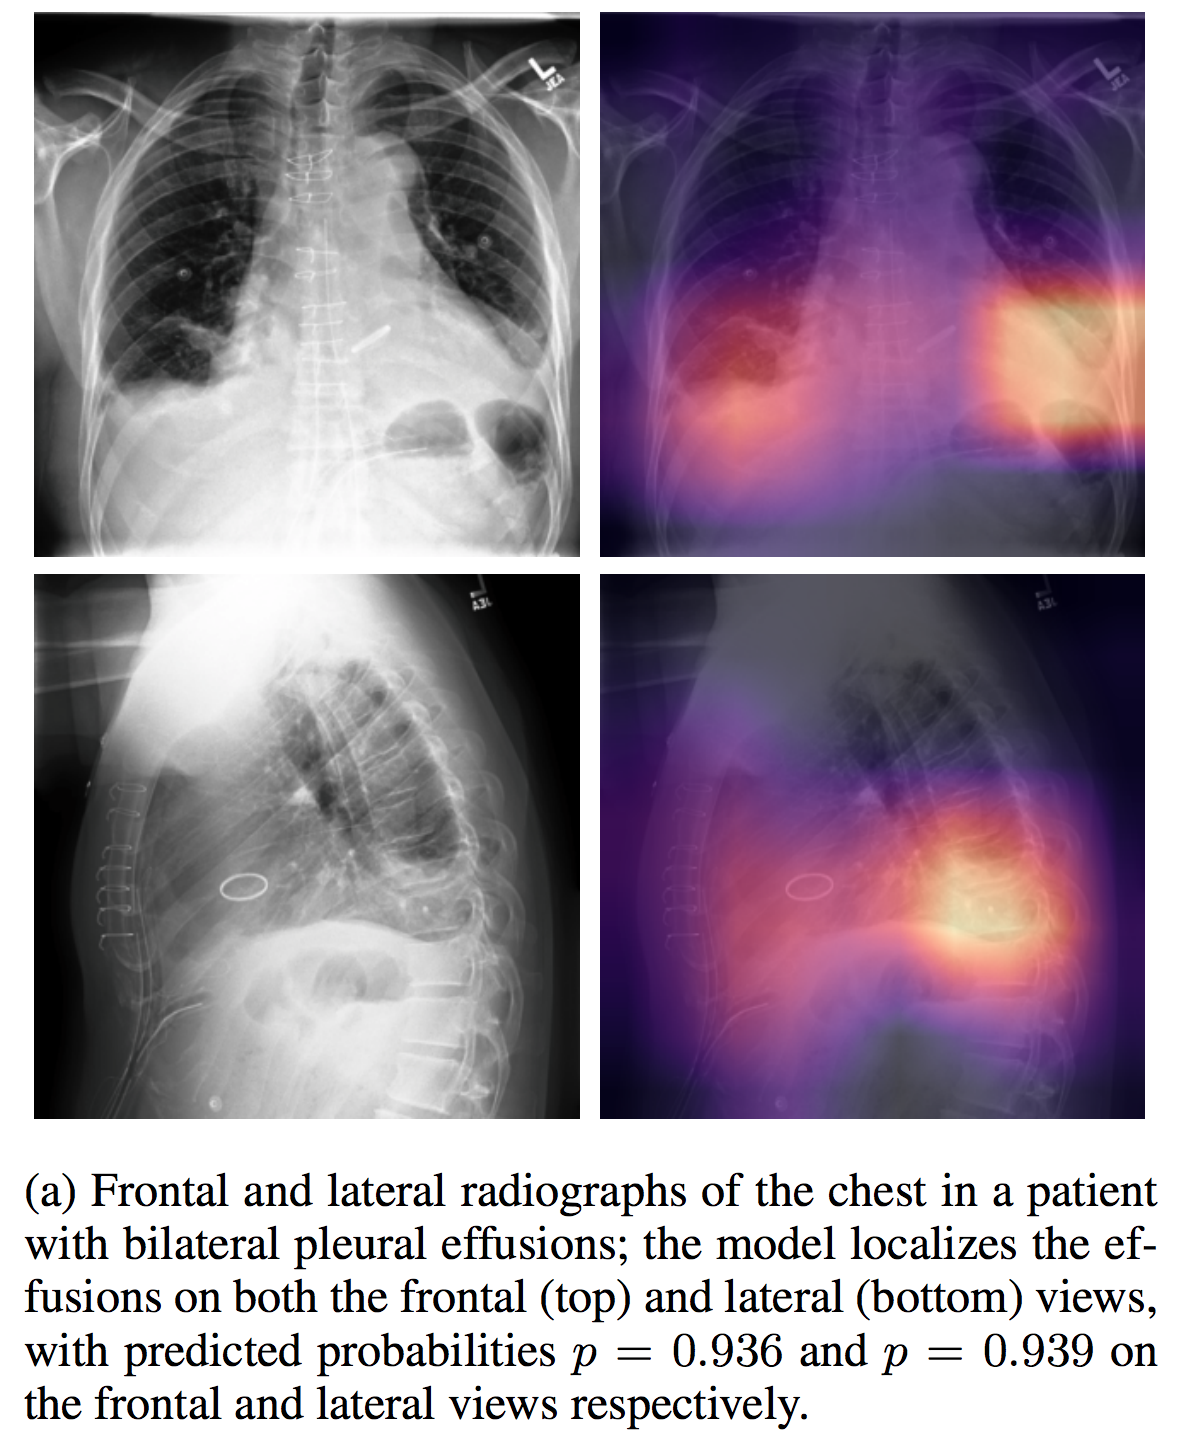

介绍论文: CheXpert: A Large Chest Radiograph Dataset with Uncertainty Labels and Expert Comparison

NIHChest Xray

| 名称 | 标注内容 | 类型 | 模态 | 数量 | 标签格式 | 文件格式 | License |

|---|---|---|---|---|---|---|---|

| NIHChest Xray | 14种肺部疾病/部分病灶位置 | 分类/检测 | CXR | 112,120 | csv | png | CC0: Public Domain |

介绍论文: ChestX-ray8: Hospital-scale Chest X-ray Database and Benchmarks on Weakly-Supervised Classification and Localization of Common Thorax Diseases